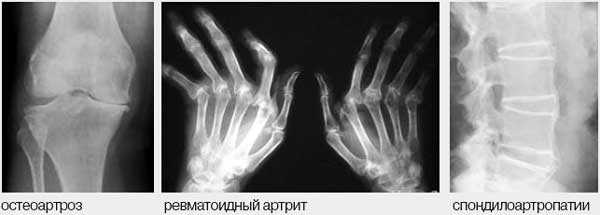

8. Наиболее часто поражение суставов и позвоночника связано с ОА, для которого характерно либо поражение 1-2 крупных суставов (локализованная форма), либо поражение мелких суставов с развитием узелков Гебердена и/или Бушара (узелковая или генерализованная форма), поражение позвоночника (спондилоартроз).

Рис. 1. Дифференциальный диагноз при болях в опорно-двигательном аппарате.